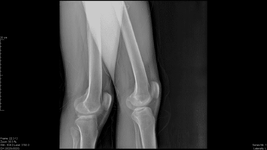

Öncelikle şunu söylemek istiyorum egzersiz kişiye özeldir ve ortopedik problemi olan kişilere mutlaka ayrıntılı bir muayeneden sonra verilmelidir. Problemin boyutu, evresi, anatomik yapınız, aktivite düzeyiniz; bunların hepsi egzersizleri değiştirebilir. Aynı problemi olan hastalara bile farklı egzersizler verilebilir bu sebeplerden dolayı. Benim size tavsiyem derdinizi dinlemeye ve ayrıntılı bir inceleme yapmaya zamanı olan kaliteli bir fizyoterapist bulun. Doktor tanısı ile beraber fzt ye gidin. Beklentilerinizi mutlaka iyi anlatın, eminim güzel sonuçlar alacaksınızdır. Bu biraz maliyetli olacaktır ama asla ameliyat olmak kadar değil.